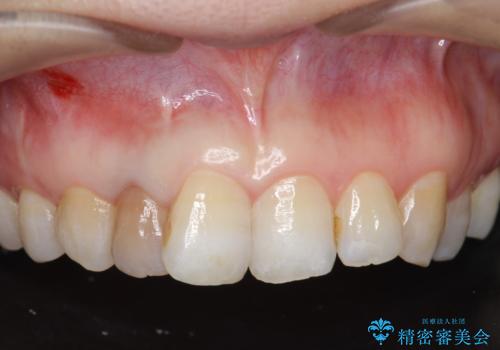

- 右上2番目の歯の変色が気になるといらっしゃった方の症例です。

再根管治療終了後、オールセラミッククラウンによる補綴を行いました。

- オールセラミッククラウン…¥100,000、仮歯…¥10,000、ファイバーコア…¥20,000費用は治療当時の料金となります